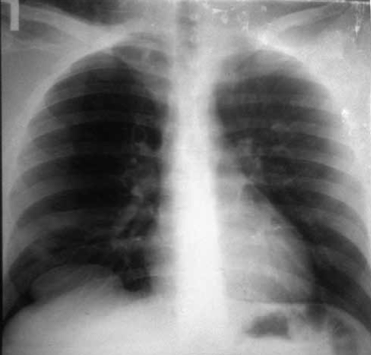

Основное место в диагностике повреждений диафрагмы принадлежит лучевым методам диагностики (7-9): рентгенологическому исследованию, компьютерной томографии. Разрыв диафрагмы установлен у 6 пострадавших при рентгенологическом исследовании (рис 1, 2), у 1 больного с тяжелой сочетанной травмой — при компьютерной томографии, у 3 больных — как интраоперационная находка. Закрытая травма порой не приводит к возникновению симптомов, которые являются патогномоничными для повреждений диафрагмы. При небольших повреждениях диафрагмы клиника, как правило, бывает скудной и стушевывается другими более тяжелыми травмами сочетанных повреждений и является находкой при рентгенологических исследованиях.

М., 20 л. Сочетанная травма. Закрытый перелом костей таза, разрыв уретры, Разрыв правого купола диафрагмы. Тяжесть повреждений по шкале оценки ВПХ П. (МТ) — 13 баллов, ВПХ (СП) — 29 (Гуманенко Е.К. 1999 г).

Больной М., 23 г. Рентгенологическая картина (прямая и боковая проекции) повреждения правого купола диафрагмы. Присасывание в плевральную полость ткани правой доли печени. Проведена лапаротомия, эпицистостомия, ушивание разрыва диафрагмы. Пациент выписан в удовлетворительном состоянии. Восстановление разрыва уретры проведено вторым этапом в урологической клинике